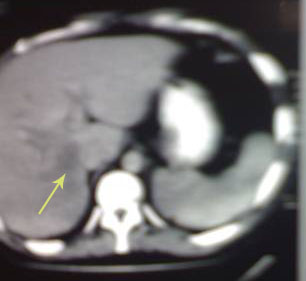

After IV umbrella of Metronidazole, (Ampicillin + Sulbactam) and (Cilastatin+Imipenem) CT guided drainage of one thousand c.c. of pus, the abscess has regressed (arrowed). Symptoms and signs subsided and general condition improved, patient discharged quite well.